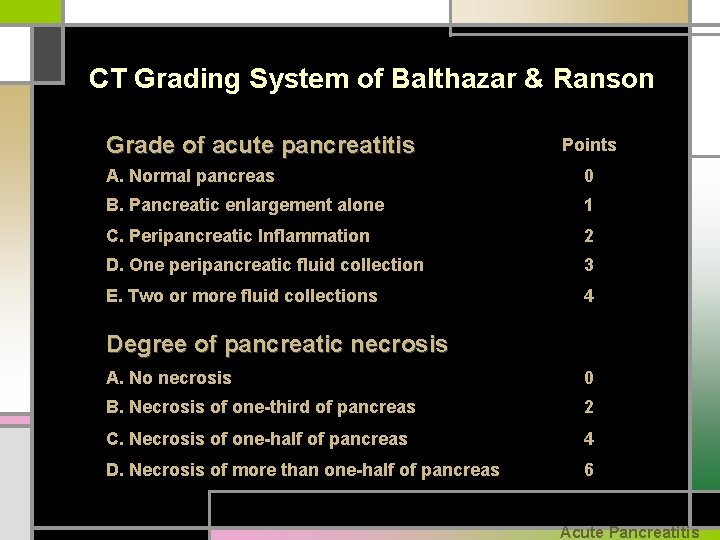

CT Grading System of Balthazar & Ranson Grade of acute pancreatitis Points A. Normal pancreas 0 B. Pancreatic enlargement alone 1 C. Peripancreatic Inflammation 2 D. One peripancreatic fluid collection 3 E. Two or more fluid collections 4 Degree of pancreatic necrosis A. No necrosis 0 B. Necrosis of one-third of pancreas 2 C. Necrosis of one-half of pancreas 4 D. Necrosis of more than one-half of pancreas 6 Acute Pancreatitis